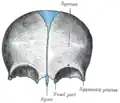

Acidentes ósseos (em inglês). Vista posterior (interna).

Acidentes ósseos (em inglês). Vista posterior (interna). -